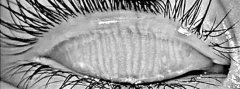

睑板腺功能障碍 详细

睑板腺功能障碍(meibomain gland dysfunction,MGD)在油性皮肤及年老者中十分常见,是蒸发过强型干眼症的主要原因。它可以被广...